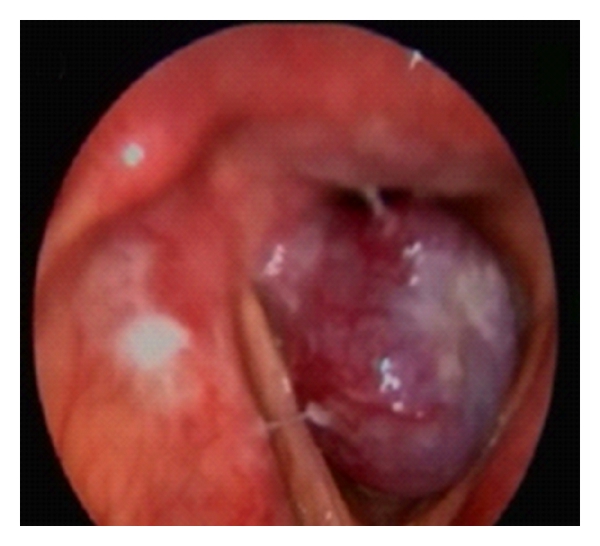

A 60-year-old male patient presented to our clinic with the complaints of hoarseness persisting for one year. He had respiratory distress appearing in the last 3-4 months. His medical history was unremarkable except for history of smoking (1 package per day for 40 years). On his videolaryngoscopic examination, a 1.5 cm vascularized, pedunculated polypoid lesion, originating from the posterior half of the vocal cord and vocal process of the arytenoid, was observed. The mass was obstructing the endolarynx, subtotally (Figure 1(a)). A tracheotomy was performed under general anesthesia to secure the airway. The mass was totally excised by endolaryngeal microsurgery. Postoperative videolaryngoscopic examination on the 4th month revealed a healed incision with no residual or recurrent mass (Figure 1(b)).

(a)

(b)

The most commonly known mesenchymal tumors of the larynx are lipomas, chondromas, vascular tumors, and paragangliomas. Schwannoma originates from the superior laryngeal nerve and may usually be encountered in a pedunculated form in the aryepiglottic plica or submucously. Chondromas may usually be located in the posterior lamina of the cricoid cartilage and cause a subglottic tumefaction [10, 11]. In the two previous laryngeal angiomyolipoma cases in the literature, the lesion was reported to have originated from the aryepiglottic fold, partially obstructing the vocal cords [6, 7]. In our case, a 1.5 cm size, vascularized, pedunculated polypoid lesion with a smooth surface originating from the vocal process of the arytenoid and posterior half of the vocal cord and subtotally obstructing the endolarynx was observed.